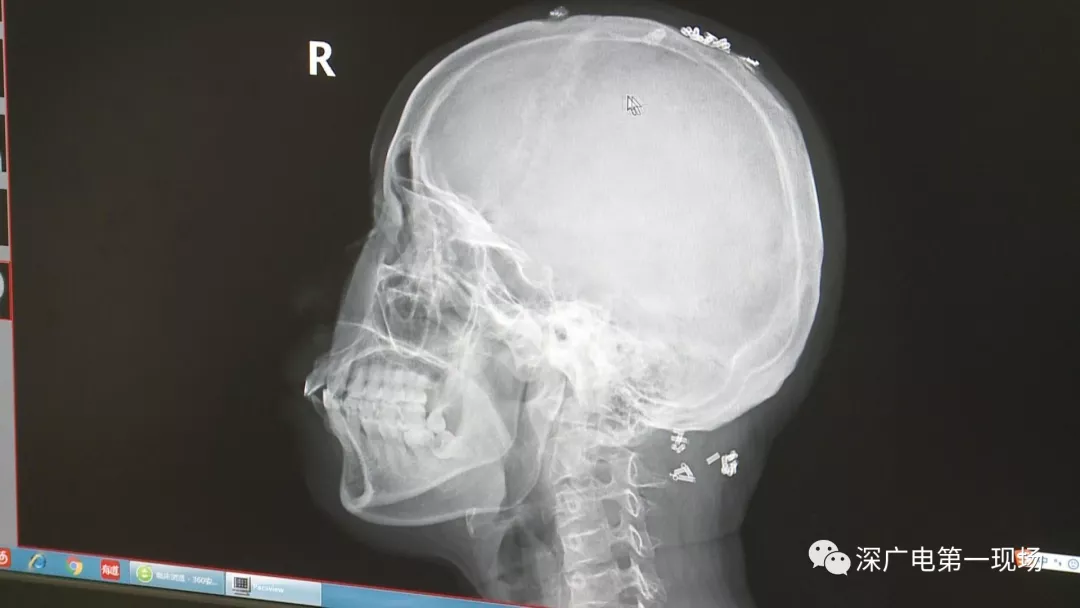

深圳一女子全身被植入彈簧圈,數(shù)量多到驚人!竟是為治這病…

彈簧圈已“寄生”三年

部分形成包塊難以取出

據(jù)了解,這位患者周身的彈簧圈已經(jīng)固定了三年多,因為患者感覺治療效果不好,就來深圳求醫(yī)。